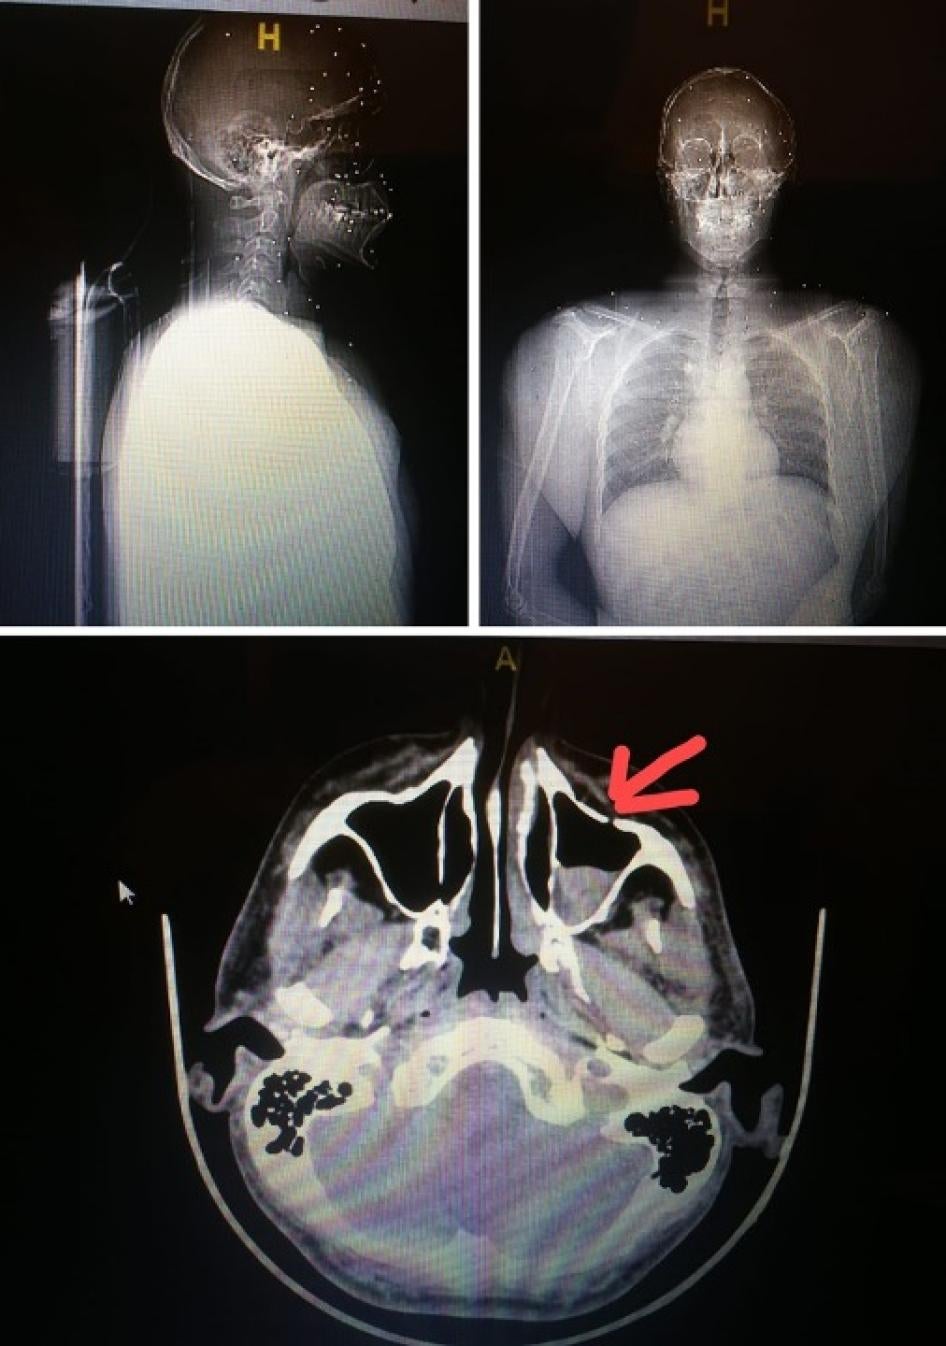

راجعت هيومن رايتس ووتش السجلّات الطبية لعمر في 8 أغسطس/آب، بما فيها صور الأشعّة السينية التي أظهرت ثلاث شظايا كبيرة من الرصاص وشظايا عديدة أصغر في رجله اليسرى. قال: "لحسن الحظ، لم تصل الرصاصة إلى عظمي. كانت قريبة من الشريان، لكنّها بالكاد لم تلامسه".

أطلقت القوات الأمنية رصاصة على عمر فأصابت أعلى فخذه الأيسر. الصورة على اليسار تظهر جرح دخول الرصاصة. تُظهر الأشعة السينية ثلاث شظايا رصاصة كبيرة وعدة شظايا أصغر في ساقه اليسرى، والصورة على اليمين تُظهر الشظايا المستخرجة من ساقه.  © 2020 تقدمة عمر

أصيب إيلي صليبا بالخردق. على اليمين، تُظهر الأشعة السينية إحدى حبات الخردق مغروسة في رأسه. © 2020 إيلي صليبا

قال إيلي صليبا، وهو طبيب كان حاضرا أثناء المظاهرة، إنّه في حوالي الساعة 5:15 مساءً، أطلقت عليه القوى الأمنية الخردق المعدني من سلاح بومب أكشن عندما كان متواجدا بين مبنييّ فيرجين ميغاستور السابق و"يو إف إيه للتأمين" قرب ساحة الشهداء. أصابت كرة خردق معدنية كتفه، ثمّ توجّه إلى سطح مبنى فيرجين ميغاستور لتصوير القوى الأمنية، بمن فيها رجال في لباس مدني وجنود، لكنّهم أطلقوا عليه الخردق مرّة أخرى من مسافة حوالي 20 متر. على الرغم من أنّه كان يضع خوذة، استقرّت ثلاث كريات معدنية في رأسه، وانتزع اثنتين على الفور. في اليوم التالي، أزال الأطبّاء الكرة الثالثة.

أصابت عشرات كريات الخردق هذا المتظاهر بثقب في فروة رأسه واستقرت تحت جيوبه الأنفية وفي عينه. © 2020 خاص

قدّم طبيب آخر صورة الأشعة السينية لمصاب بعشرات حبيبات الخردق دون الكشف عن اسم المتظاهر. قال الطبيب إن كمية الخردق وحقيقة أنها ثقبت فروة رأس المصاب تشير إلى أن القوى الأمنية أطلقت النار عليه من مسافة قريبة جدا. استقرت كريات الخردق تحت الجيوب الأنفية في الجمجمة وفي عين المتظاهر.